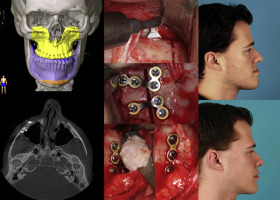

2. QUADANGULAR LEFORT + BSSO + GENIOPLASTY

quadangular lefort less risky than MLF3/LF2)

2. QUADANGULAR LEFORT + BSSO + GENIOPLASTY

quadangular lefort